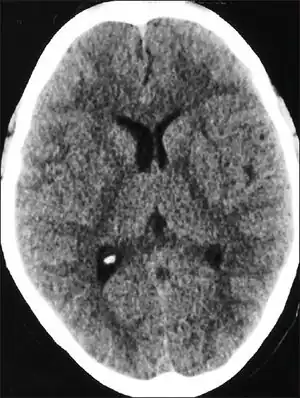

| CT scan of the head showing diffuse effacement of cerebral sulci and compression of the ventricles in a case with high altitude cerebral edema[1] | |

People with HACE have an elevated white blood cell count, but otherwise their blood count and biochemistry are normal. If a lumbar puncture is performed, it will show normal cerebral spinal fluid and cell counts but an increase in pressure.[10] In one study, CT scans of patients with HACE exhibited ventricle compression and low density in the cerebellum.[10] Only a few autopsies have been performed on fatal cases of HACE;[11] they showed swollen gyri, spongiosis of white matter, and compressed sulci. There was some variation between individuals, and the results may not be typical of HACE deaths.[11]

Recovery varies between days and weeks,[11] but most recover in a few days.[28] After the condition is successfully treated, it is possible for climbers to reascend. Dexamethesone should be discontinued, but continual acetazolamide is recommended.[32] In one study, it took patients between one week and one month to display a normal CT scan after suffering from HACE.[10]